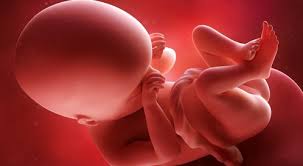

الأسبوع 10 من الحمل الأعراض حجم الجنين التغيرات في جسمك والمزيد

تطورات الام والجنين في الاسبوع العاشر من الحمل موسوعة

الجنين في الأسبوع العاشر موضوع

علامات الاسبوع العاشر من الحمل ويب طب